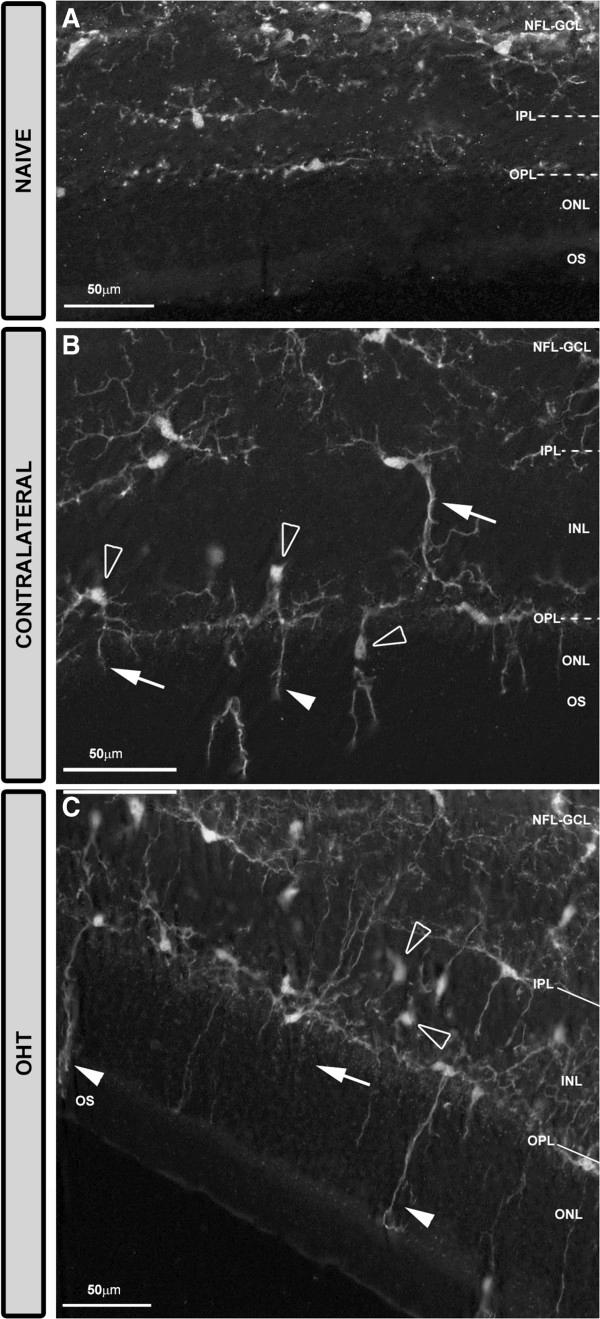

Glaucomatous optic neuropathy, a leading cause of blindness, can progress despite control of intraocular pressure - currently the main risk factor and target for treatment. Glaucoma progression shares mechanisms with neurodegenerative disease, including microglia activation. In the present model of ocular hypertension (OHT), we have recently described morphological signs of retinal microglia activation and MHC-II upregulation in both the untreated contralateral eyes and OHT eyes. By using immunostaining, we sought to analyze and quantify additional signs of microglia activation and differences depending on the retinal layer.

Two groups of adult Swiss mice were used: age-matched control (naïve, n = 12), and lasered (n = 12). In the lasered animals, both OHT eyes and contralateral eyes were analyzed. Retinal whole-mounts were immunostained with antibodies against Iba-1, MHC-II, CD68, CD86, and Ym1. The Iba-1+ cell number in the plexiform layers (PL) and the photoreceptor outer segment (OS), Iba-1+ arbor area in the PL, and area of the retina occupied by Iba-1+ cells in the nerve fiber layer-ganglion cell layer (NFL-GCL) were quantified.

The main findings in contralateral eyes and OHT eyes were: i) ameboid microglia in the NFL-GCL and OS; ii) the retraction of processes in all retinal layers; iii) a higher level of branching in PL and in the OS; iv) soma displacement to the nearest cell layers in the PL and OS; v) the reorientation of processes in the OS; vi) MHC-II upregulation in all retinal layers; vii) increased CD68 immunostaining; and viii) CD86 immunolabeling in ameboid cells. In comparison with the control group, a significant increase in the microglial number in the PL, OS, and in the area occupied by Iba-1+ cells in the NFL-GCL, and significant reduction of the arbor area in the PL. In addition, rounded Iba-1+ CD86+ cells in the NFL-GCL, OS and Ym1+ cells, and rod-like microglia in the NFL-GCL were restricted to OHT eyes.

青光眼性视神经病变是失明的主要原因之一,尽管眼压得到控制(目前眼压是主要危险因素和治疗靶点),病情仍可能进展。青光眼进展与神经退行性疾病有共同机制,包括小胶质细胞激活。在当前的高眼压(OHT)模型中,我们最近描述了未治疗的对侧眼和高眼压眼中视网膜小胶质细胞激活的形态学迹象以及MHC-II上调。通过免疫染色,我们试图分析和量化小胶质细胞激活的其他迹象以及视网膜各层之间的差异。

使用两组成年瑞士小鼠:年龄匹配的对照组(未处理,n = 12)和激光照射组(n = 12)。在激光照射的动物中,对高眼压眼和对侧眼均进行分析。视网膜全层标本用抗Iba-1、MHC-II、CD68、CD86和Ym1的抗体进行免疫染色。对视神经纤维层-神经节细胞层(NFL-GCL)中丛状层(PL)和光感受器外段(OS)的Iba-1+细胞数量、PL中Iba-1+树突面积以及Iba-1+细胞占据的视网膜面积进行量化。

对侧眼和高眼压眼的主要发现如下:i)NFL-GCL和OS中有阿米巴样小胶质细胞;ii)所有视网膜层的突起回缩;iii)PL和OS中分支水平更高;iv)PL和OS中细胞体向最近的细胞层移位;v)OS中突起重新定向;vi)所有视网膜层中MHC-II上调;vii)CD68免疫染色增加;viii)阿米巴样细胞中有CD86免疫标记。与对照组相比,PL、OS以及NFL-GCL中Iba-1+细胞占据区域的小胶质细胞数量显著增加,PL中树突面积显著减少。此外,NFL-GCL、OS中的圆形Iba-1+ CD86+细胞和Ym1+细胞以及NFL-GCL中的杆状小胶质细胞仅限于高眼压眼。